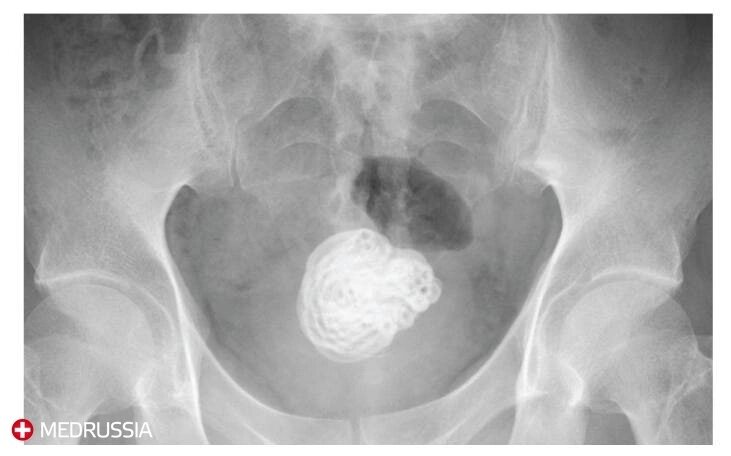

Пациентом был 49-летним мужчиной без каких-либо психических расстройств в анамнезе. Он прошел медицинское обследование в местном отделении неотложной помощи и был направлен для исследования инородного тела в мочевом пузыре, которое было выявлено при ультразвуковом исследовании. На простом рентгеновском снимке было обнаружено извитое инородное тело диаметром около 5 см, а также утолщение в стенке мочевого пузыря. Цистоскопия показала камнеобразную природу инородного тела. По словам пациента, примерно два года назад он вставил виниловую трубку в уретру для мастурбации и не смог ее извлечь; она оставалась в этом положении, из-за чего он испытывал боль в уретре в течение первых шести месяцев после инцидента. Поскольку инородное тело было большим, операция считалась сложной. Инородное тело было в длину примерно 140 см и было успешно удалено.

На простом рентгеновском снимке было обнаружено извитое инородное тело диаметром около 5 см, а также утолщение в стенке мочевого пузыря.